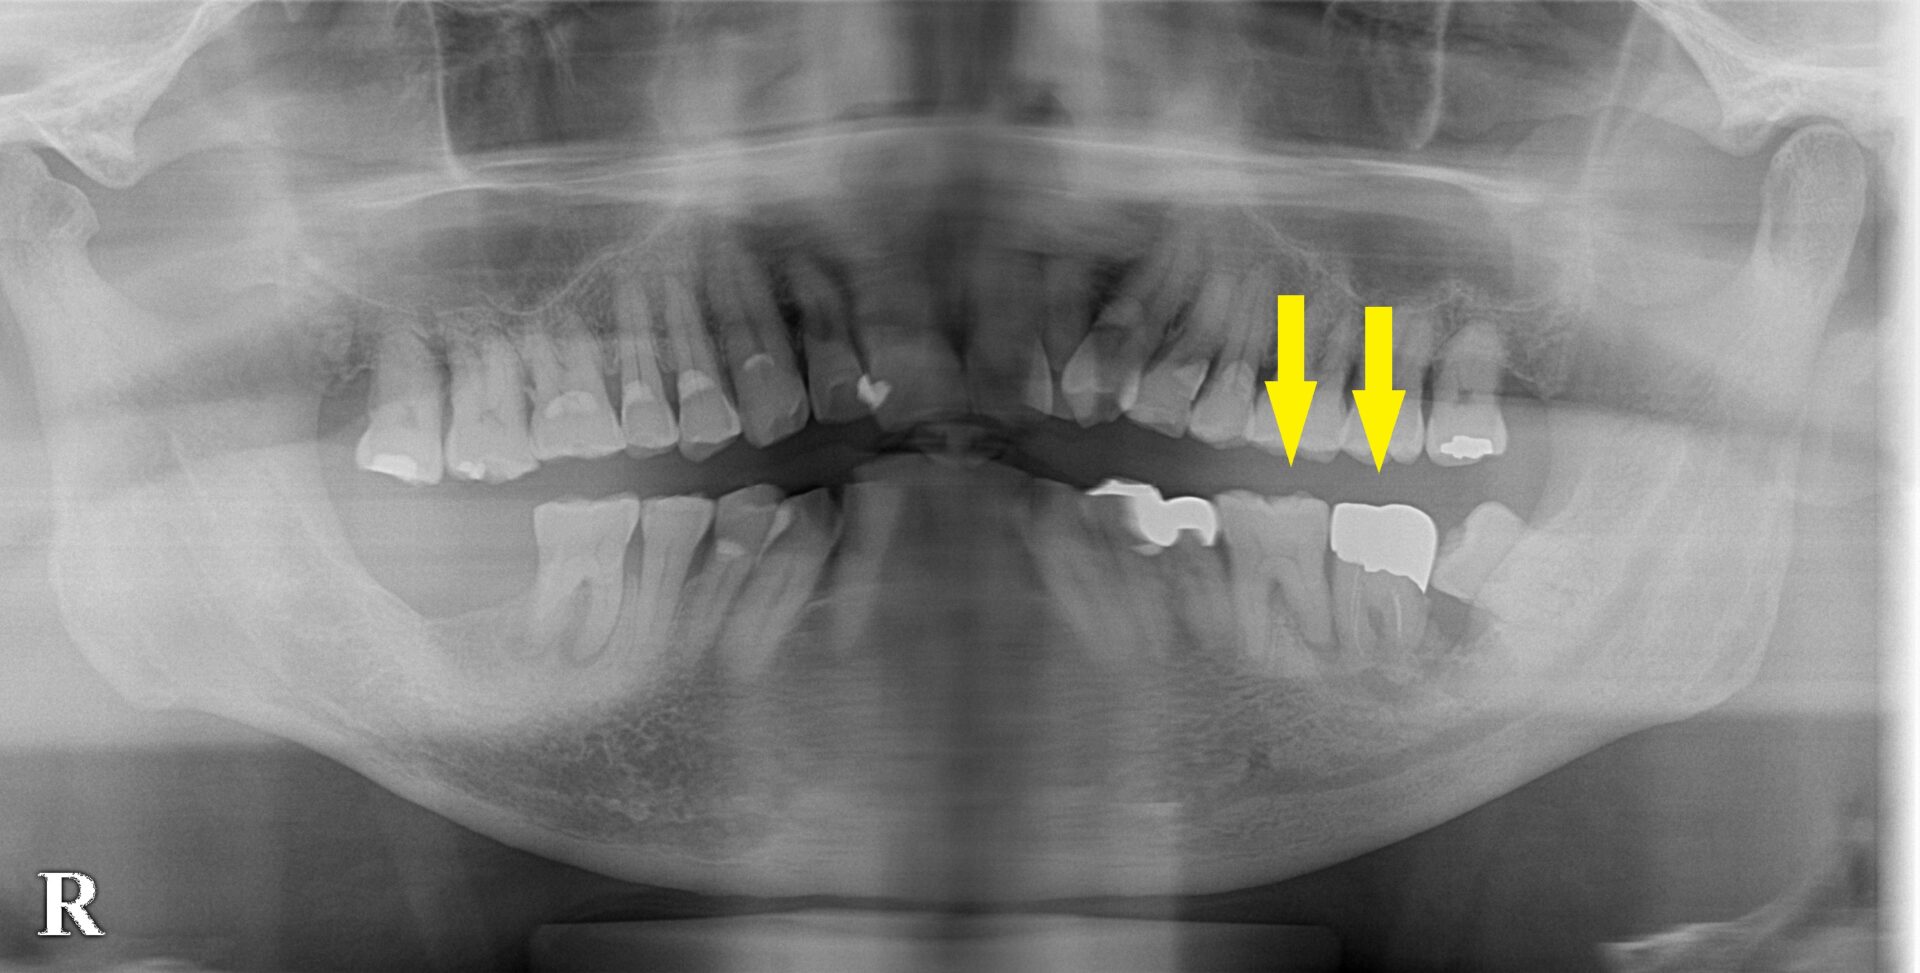

患者様は名古屋在住の70代男性。

左下顎の大臼歯が炎症を繰り返し、周囲の骨が大きく吸収されて、グラグラして痛いので、抜歯してインプラントにしたいとのご希望で来院されました。

まずは抜歯して、治癒を待つことにしました。

後ろの親知らずも一緒に抜歯しました。